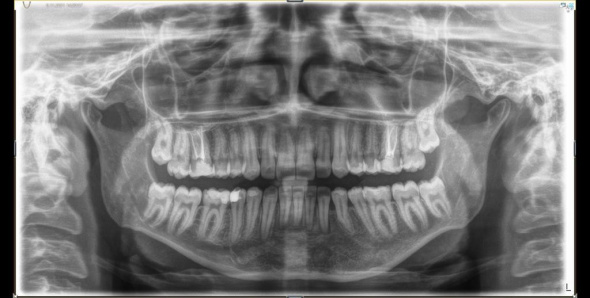

Gömülü bir dişle birlikte 7,5 santimetrelik kistin çene bölgesindeki sinirleri ve kemik yapısını etkilediğini belirten ESOGÜ Ağız, Diş ve Çene Cerrahisi Anabilim Dalı Öğretim Üyesi Doç. Dr. Nesrin Saruhan, hazırlıksız yapılacak ameliyatın büyük risk taşıdığını belirtti. Sinirlerde uyuşukluk ve çene kemiğinde kırık oluşmasını engellemek için kist küçültme ameliyatı yaptıklarını belirten Doç. Dr. Nesrin Saruhan, “Tuğçe bize geldiğinde 15 yaşındaydı. Alt çenesinde sağdan sola uzanan 7,5 santimetrelik oldukça büyük bir kisti vardı. Bununla ilgili birkaç merkeze gitmiş ama Eskişehir’de bu tedavinin yapılamayacağı bilgisi verilmiş. Kendisi kliniğimize geldiğinde önce radyolojik muayenelerimizi yaptık. Oldukça büyük bir kist vardı. Hem sinirle ilişkiliydi hem de alt çene kemiğini zayıflatmıştı. Bir de gömülü dişi vardı. İlk etapta parça alıp biyopsisini yaptık. Kist tanısını koyduktan sonra iki aşamalı tedavi planladık.